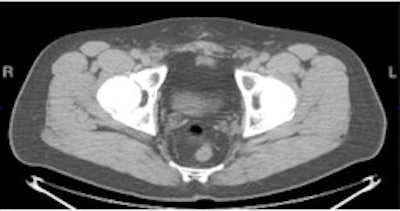

Another research study being presented at the SNM conference this week involves a new molecular imaging agent that could improve the diagnosis of recurrent prostate cancer and determine the best possible course of treatment for patients.

The agent, developed by Mark Goodman, MD, at Emory University in Atlanta, consists of a fluorine-based radioisotope paired with a synthetic amino-acid analog similar to the naturally occurring amino acid L-leucine (anti-F-18 FACBC).

| PET/CT with anti-F-18 FACBC (below) shows left obturator lymph node better than CT (top) and PET (above) images alone. |

Not only was the agent shown to be highly accurate in differentiating recurrent tumors in the prostate from metastatic cancer, but researchers believe the agent could help change patient treatment and improve the prognosis for prostate cancer patients.